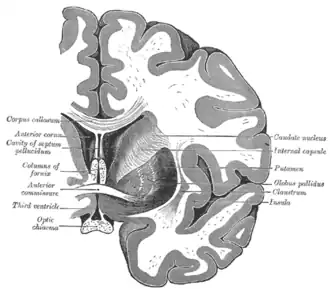

Transverse cut of brain (horizontal section), basal ganglia is blue | |

Ventricles of brain and basal ganglia. Superior view, horizontal section, deep dissection

Ventricles of brain and basal ganglia. Close-up of preceding image